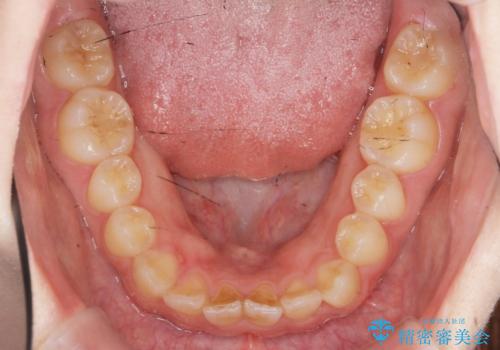

- ねじれの目立つ前歯を改善したいと、矯正治療を希望され来院されました。

インビザラインの不得意な上顎前歯のねじれの改善を、マウスピース矯正を行う前に前歯のみの部分ワイヤー矯正を行うことで治療期間の短期化を目指します。

上顎前歯のねじれはマウスピースで治りづらいため、マウスピース矯正の治療期間の長期化をきたしやすい歯列不正です。

マススピース矯正を始める前に、部分ワイヤー矯正を行うことで治療の短期間化・良好な仕上がりを達成することができました。